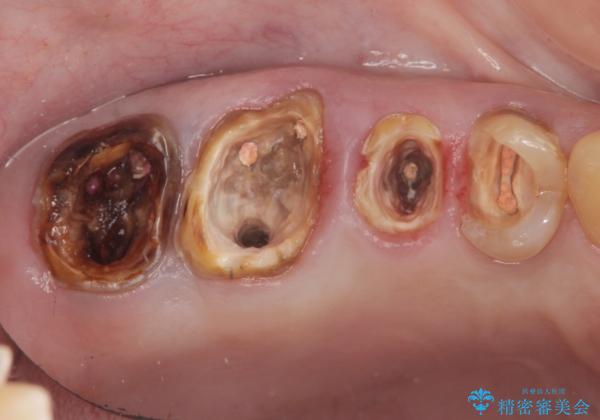

根管治療・歯周外科を行い歯を残した、複合的虫歯治療

- 近医で「根尖の病変が大きく、残すことができない、歯を抜くしかない。」、と言われ歯を抜く以外の手段がないかを相談しに来院されました。

検査の結果、根管・クリアランス・虫歯といった複合的な問題が認められ、以下のような治療計画を進めることとしました。

根尖病変 →マイクロスコープを用いた精密根管治療の実施

一つ一つの工程を丁寧に行うことで、根尖病変の改善傾向も見られ、安定した歯周環境を整えることができました。